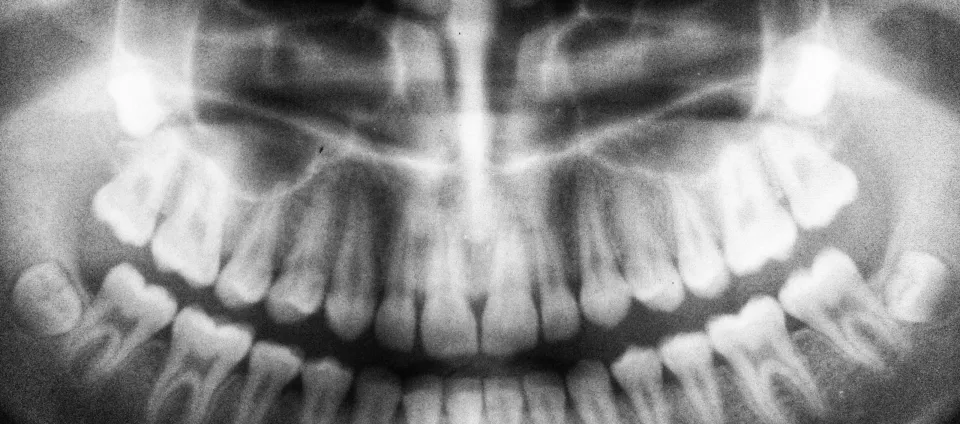

Black and white panoramic dental X-ray showing full adult teeth and jaw structure

Digital X-Rays

We use low-radiation imaging that delivers crystal-clear pictures in seconds. We can spot what needs attention and walk you through it together. You don't have to deal with the old-school wait or mess of film.